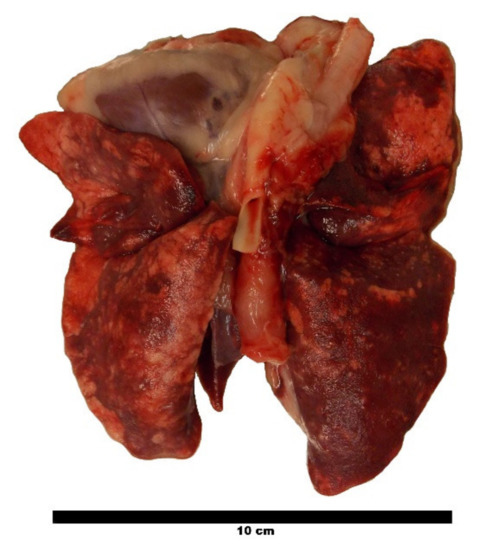

3. Discussion

4.7. Parasitological Necropsy